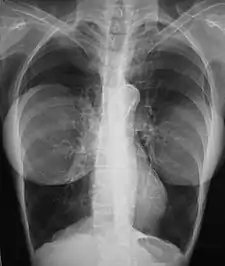

The presence of radiologically opaque breast implants (either saline or silicone) might interfere with the radiographic sensitivity of the mammograph, that is, the image might not show any tumor(s) present. In this case, an Eklund view mammogram is required to ascertain either the presence or the absence of a cancerous tumor, wherein the breast implant is manually displaced against the chest wall and the breast is pulled forward, so that the mammograph can visualize a greater volume of the internal tissues; nonetheless, approximately one-third of the breast tissue remains inadequately visualized, resulting in an increased incidence of mammograms with false-negative results.[114][115]

The breast cancer studies Cancer in the Augmented Breast: Diagnosis and Prognosis (1993) and Breast Cancer after Augmentation Mammoplasty (2001) of women with breast implant prostheses reported no significant differences in disease-stage at the time of the diagnosis of cancer; prognoses are similar in both groups of women, with augmented patients at a lower risk for subsequent cancer recurrence or death.[116][117] Conversely, the use of implants for breast reconstruction after breast cancer mastectomy appears to have no negative effect upon the incidence of cancer-related death.[118] That patients with breast implants are more often diagnosed with palpable—but not larger—tumors indicates that equal-sized tumors might be more readily palpated in augmented patients, which might compensate for the impaired mammogram images.[119] The ready palpability of the breast-cancer tumor(s) is consequent to breast tissue thinning by compression, innately in smaller breasts a priori (because they have lesser tissue volumes), and that the implant serves as a radio-opaque base against which a cancerous tumor can be differentiated.[120]

The breast implant has no clinical bearing upon lumpectomy breast-conservation surgery for women who developed breast cancer after the implantation procedure, nor does the breast implant interfere with external beam radiation treatments (XRT); moreover, the post-treatment incidence of breast-tissue fibrosis is common, and thus a consequent increased rate of capsular contracture.[121] There is tentative evidence that women who have had breast augmentation, have worse breast cancer prognosis.[122] The use of implants for breast reconstruction after breast cancer mastectomy appears to have no negative effect upon cancer-related death.[118][123]

There have been multiple reported cases of other adverse effects of mammography of women with breast implants; ruptures resulting from pressure exerted on the breast implant make up a majority of these cases.[124] Compression may also lead to pain or exacerbate already existing pain in the breasts.[124]